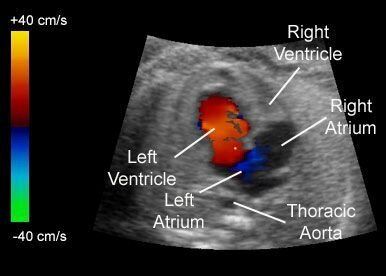

2D Echo and Color Doppler Heart - CD Heart

The purpose of this study is to determine the size of your heart, to evaluate how well your heart is functioning or pumping and to assess the struc...